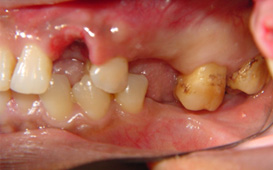

咬合崩塌 / 上牙下墜 / 下牙上長 / 前牙飆出 / 傾倒 / 蛀牙 / 牙周病缺牙未重建 - 臨床實例

上面的牙往下墜,下面的牙往上長,前面的牙往外飆 – 咬合崩塌牙周病,蛀牙;這些現象必然發生,時間越久,問題越大,而且除非藉由矯正及其他牙科治療,無法修正。

缺牙導致牙齒移位 - 臨床實例二